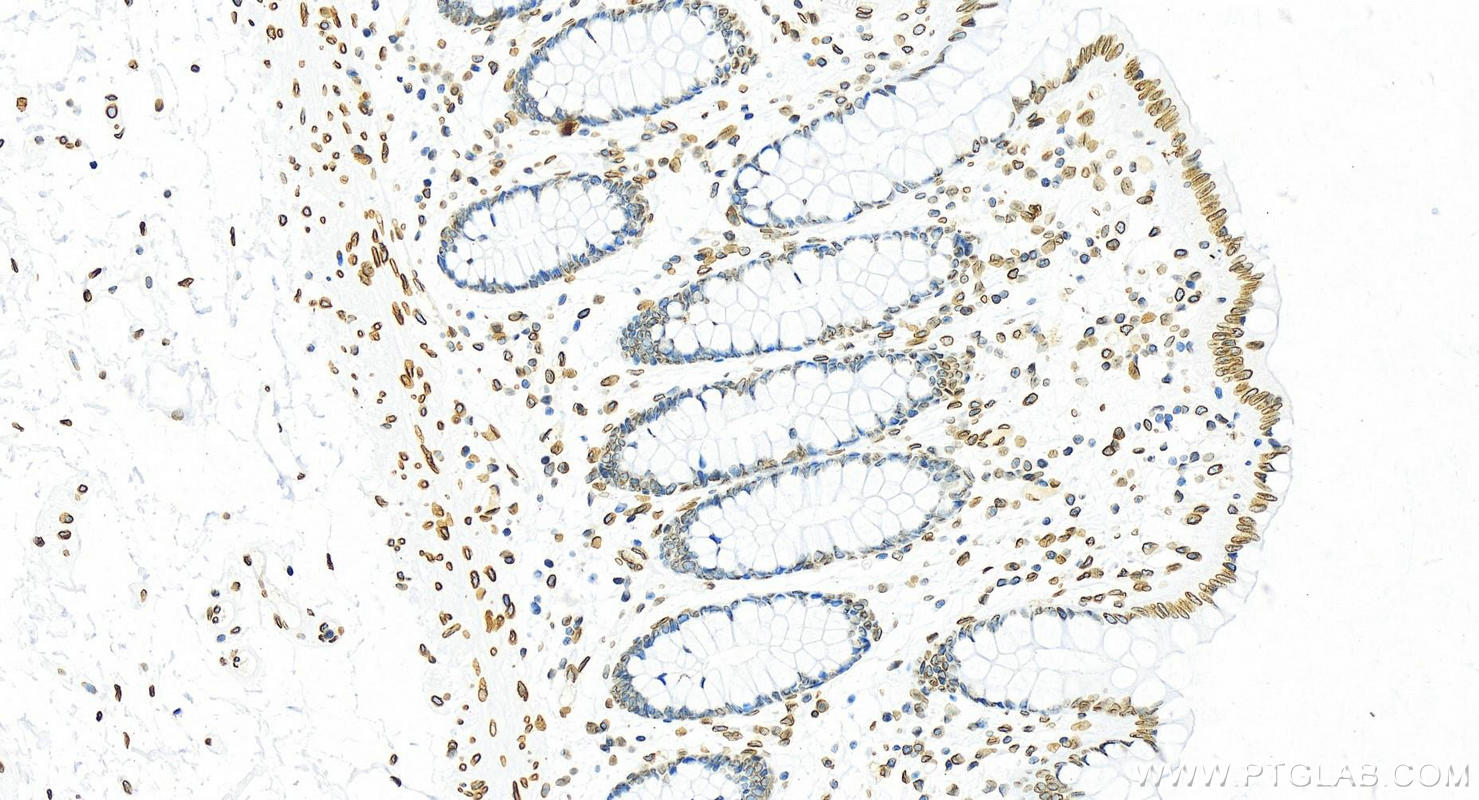

82801-4-PBS targets Lamin B2 in WB, IHC, IF/ICC, FC (Intra), Indirect ELISA applications and shows reactivity with human samples.